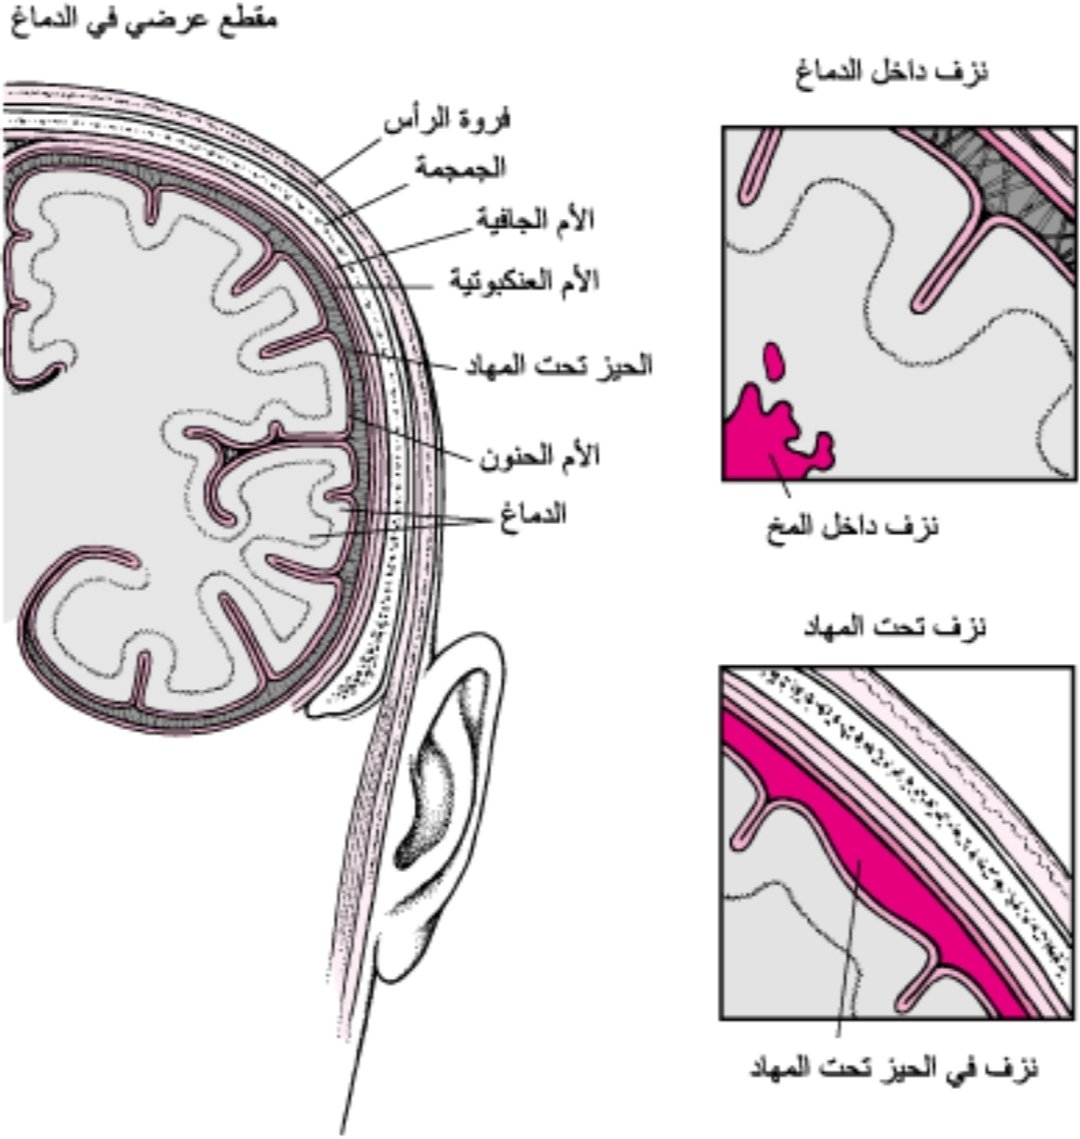

#السكته_الدماغيه_النزيفيه

بسبب إنفجار احد الشرايين او انسداد الاوردة

💥انواعها

🧠حول انسجة المخ

🧠داخل انسجة المخ

🧠داخل تجاويف المخ

💥انواعها

🧠حول انسجة المخ

🧠داخل انسجة المخ

🧠داخل تجاويف المخ

💥هنالك حالات يزداد فيها الضغط داخل الجمجمه

💥بسبب

🧠تجمع السوائل

🧠غزارة النزيف

🧠 كبر حجم التجمع الدموي

💥ولان العظم لايتمدد

فقدرته محدده لاستيعاب الحجم الزائد